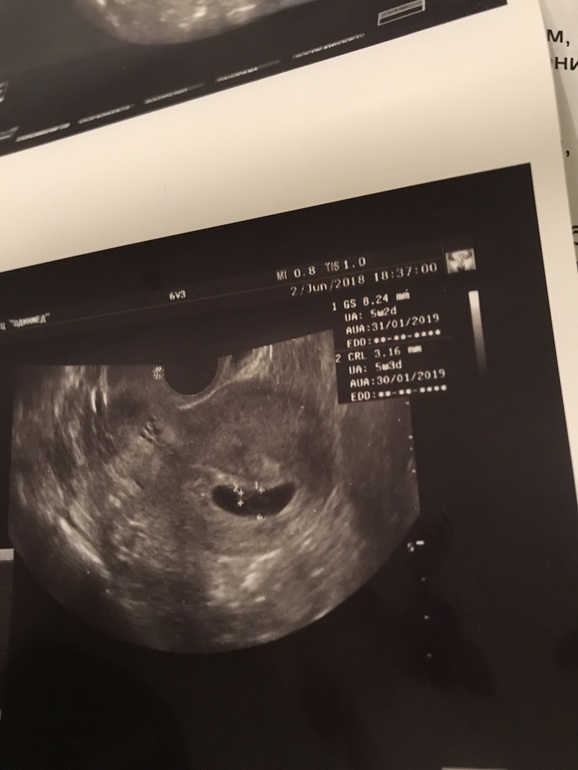

Сейгодня акушерских 7+6. Заныл сильно правый бок в районе желтого тела. И долго так... стала переживать, что что-то не так. Пошла в мед.центр. Там гинеколог сразу сказала ложиться на УЗИ. В итоге предположила замершую беременность 5-6 недель. Сердцебиения нет, Ктр 3,16 мм, плодный мешок 5 мм, размер плодного яйца свд 8 мм. Рекомендация лечь в стационар. Позвонила своему гинекологу, сказала завтра к ним в клинику на УЗИ и сдать хгч.